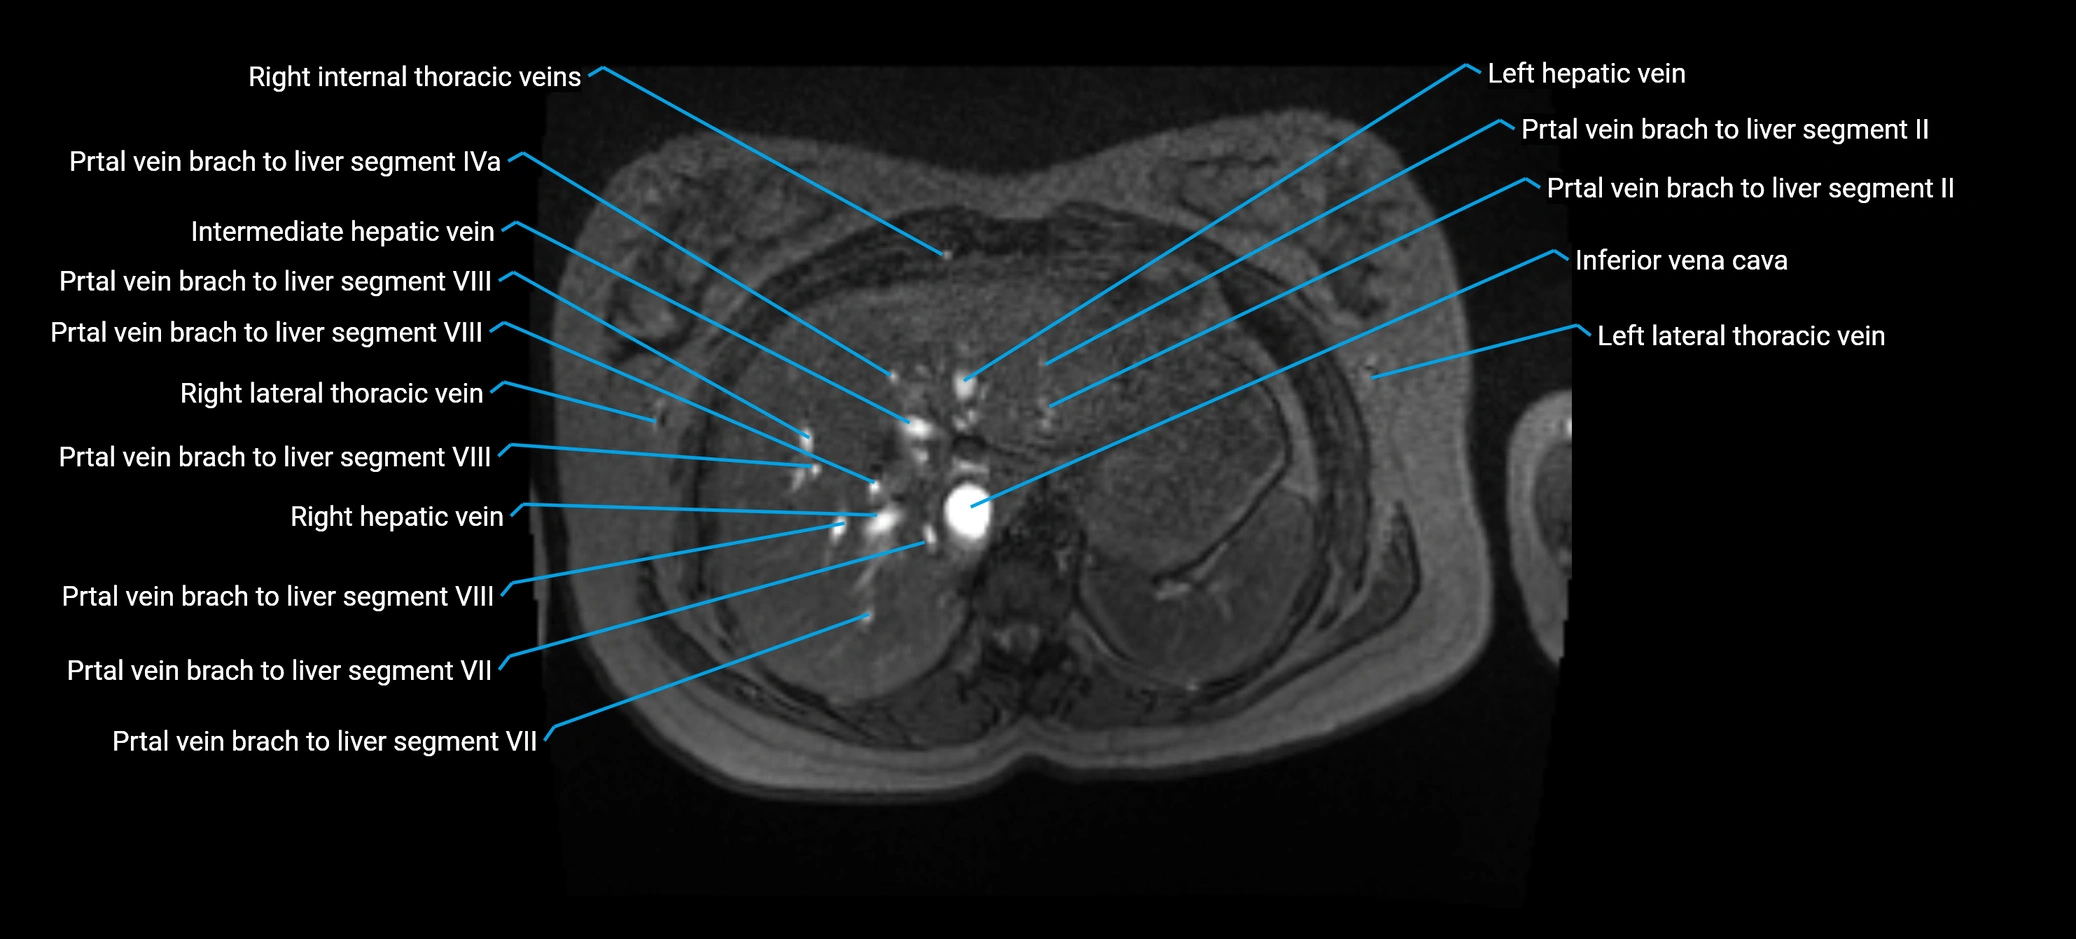

The anterior right branch of the portal vein is a major intrahepatic division of the right portal vein. After the main portal vein bifurcates into right and left branches, the right portal vein divides into anterior and posterior segmental branches.

The anterior right branch supplies the anterolateral liver segments (Segment V) and anteromedial liver segments (Segment VIII) within the right hepatic lobe. It operates as a key vascular route delivering nutrient-rich portal venous blood to the central and superior right liver.

• Clearly shows branching pattern of right portal vein into anterior and posterior branches

• Best in coronal or axial reconstructions for segmental mapping

• Enhances brightly and homogeneously during the portal venous phase

• Clearly delineates branching into segments V and VIII

• Best sequence for evaluating patency, caliber, and anatomic variants

MRI image

image